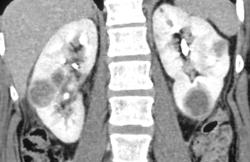

Focal Renal Abscesses